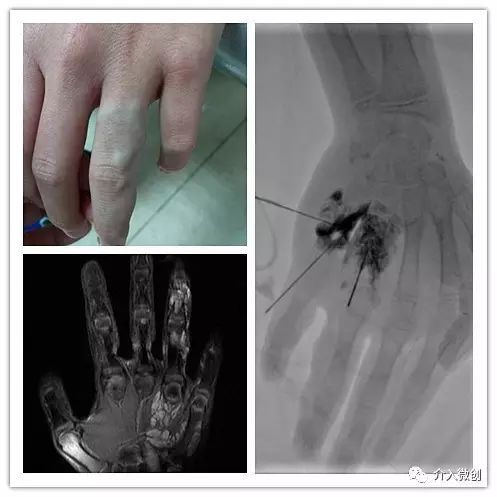

左手静脉畸形

男性患儿,MRI检查示左手掌小鱼际肌侧,左手无名指、左手示指多发静脉畸形。

DSA引导下行经皮穿刺畸形静脉泡沫硬化术。